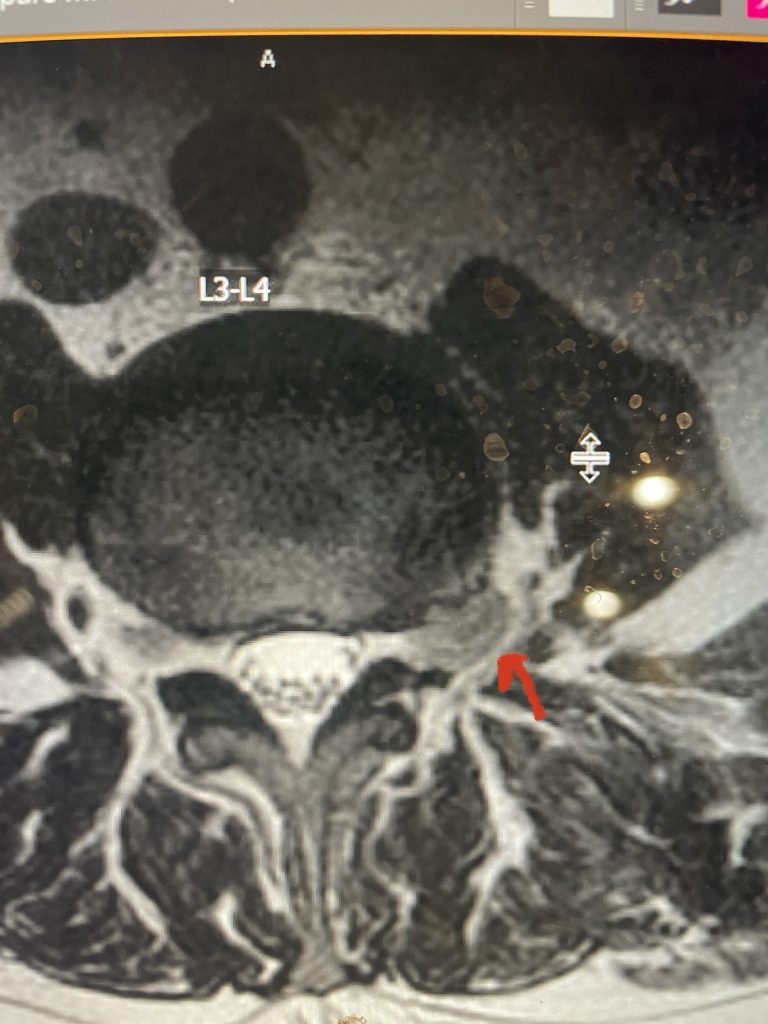

Fig 6: Axial T2-weighted lumbar MRI revealing a large extraforaminal disc herniation with severe compression of the left L3 nerve (red arrow).